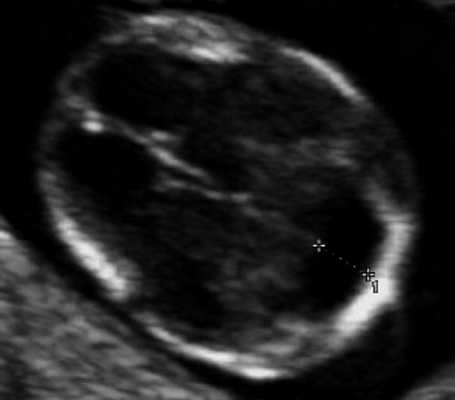

В аксиальном срезе головки привлекает к себе внимания то, что сосудистые сплетения расположены ближе к затылочной кости, чем к лобным костям. Расстояние между лобными костями и передним контуром сосудистых сплетений увеличено (указано стрелками)

В аксиальном срезе головки четверохолмие (обведено пунктиром) также расположено ближе к затылочным костям. Ножки мозга удлинены. 1-ножки мозга. 2-таламусы